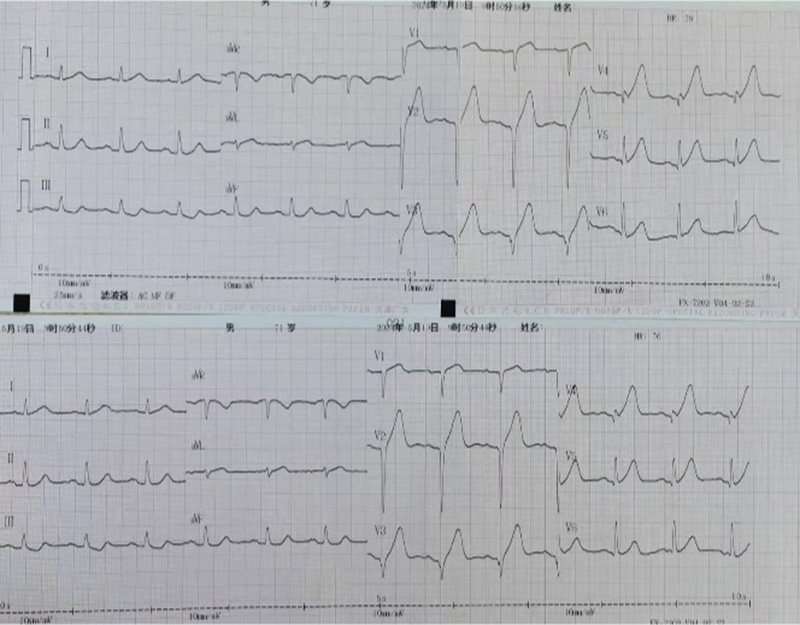

5月19日,对家住咸阳市秦都区的王先生来说,本来阳光明媚的天气却因突发的胸闷和胸痛,蒙上了一层阴影。随着症状持续加重,家人紧急将他送到陕西省核工业二一五医院。 二一五医院国家级胸痛中心迅速启动应急预案,随着绿色通道迅速打开,...